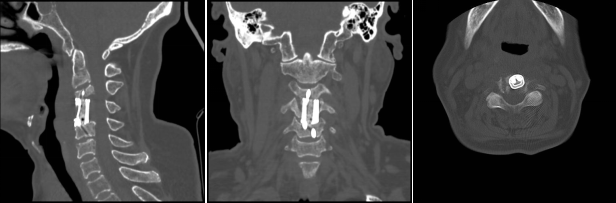

經(jīng)過(guò)周密細(xì)致的術(shù)前討論,脊柱外科團(tuán)隊(duì)最終決定為該患者擬行頸椎病灶清除、椎管減壓+植骨融合術(shù),考慮患者高齡,又有骨質(zhì)疏松,為更好保障重建穩(wěn)定性,采用3D打印進(jìn)行術(shù)前規(guī)劃設(shè)計(jì)假體進(jìn)行植入,此款融合器是國(guó)內(nèi)首款SLM激光打印融合器,具有解剖匹配、骨融合確切等優(yōu)勢(shì),為取得優(yōu)良手術(shù)效果打下了堅(jiān)實(shí)基礎(chǔ)。

經(jīng)過(guò)多學(xué)科會(huì)診(MDT),完善術(shù)前相關(guān)準(zhǔn)備后,由蘇光輝主任主刀,帶領(lǐng)團(tuán)隊(duì)錢(qián)軍、鄧三東等,精準(zhǔn)完成病灶清除、椎管減壓、植入3D打印cage等流程,在麻醉師、手術(shù)室的全力配合下,整臺(tái)手術(shù)一氣呵成,手術(shù)順利。

術(shù)后影像學(xué)顯示,植入內(nèi)植物位置滿(mǎn)意,與終板匹配性良好,穩(wěn)定性佳。術(shù)后患者生命體征平穩(wěn),癥狀明顯緩解,活動(dòng)良好,目前已出院。